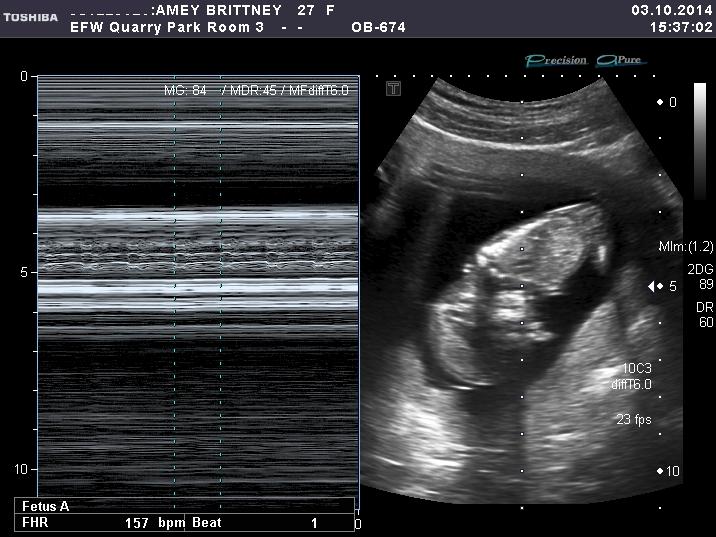

I just had my 12week scan and can't for the life of me figure out this nub theory thing!  I am stumped, so maybe you all can help me out, what are your guesses... boy or girl?

help me out, what are your guesses... boy or girl?